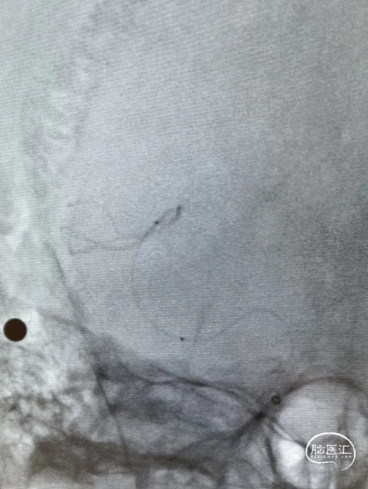

6、3mm x 10mm APOLLO成形

7、术后造影

8、术后MR